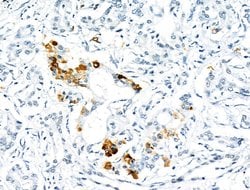

| Immunohistochemistry (Paraffin), Western Blot, Immunocytochemistry | |